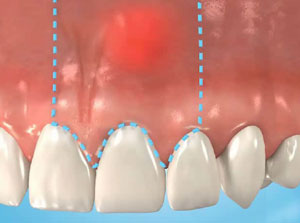

Eine Wurzelspitzenentfernung (auch Wurzelspitzenresektion genannt) wird bei einer entzündeten Zahnwurzel angewandt. Ursache hierfür kann beispielsweise eine sehr weitreichende Karieserkrankung sein. Dabei wird nur die Wurzelspitze und das die Wurzelspitze umgebende entzündete Gewebe entfernt. Man verhindert damit die Ausbreitung einer Infektion auf den Knochen und die Entstehung von Abszessen. Das Ziel der Wurzelspitzenresektion ist es den Zahn zu erhalten. Eine Wurzelspitzenentfernung kann auch bei Brüchen der Wurzel, Tumorverdacht oder Hohlräumen (Zysten) notwendig sein.

Bei der Wurzelspitzenentfernung durchtrennt der Zahnarzt über der betreffenden Zahnwurzel das Zahnfleisch und die Knochenhaut. Das Zahnfleisch wird vom Knochen weggeschoben, bis dieser frei zugänglich ist. Um an die Wurzelspitze zu gelangen wird der Knochen mit einer speziellen Knochenfräse abgetragen. Anschließend kürzt der Zahnarzt die entzündete Wurzelspitze mit einer länglichen Fräse um einige Millimeter. Dabei werden feine verästelte Ausläufer des Wurzelkanals möglichst mit entfernt.